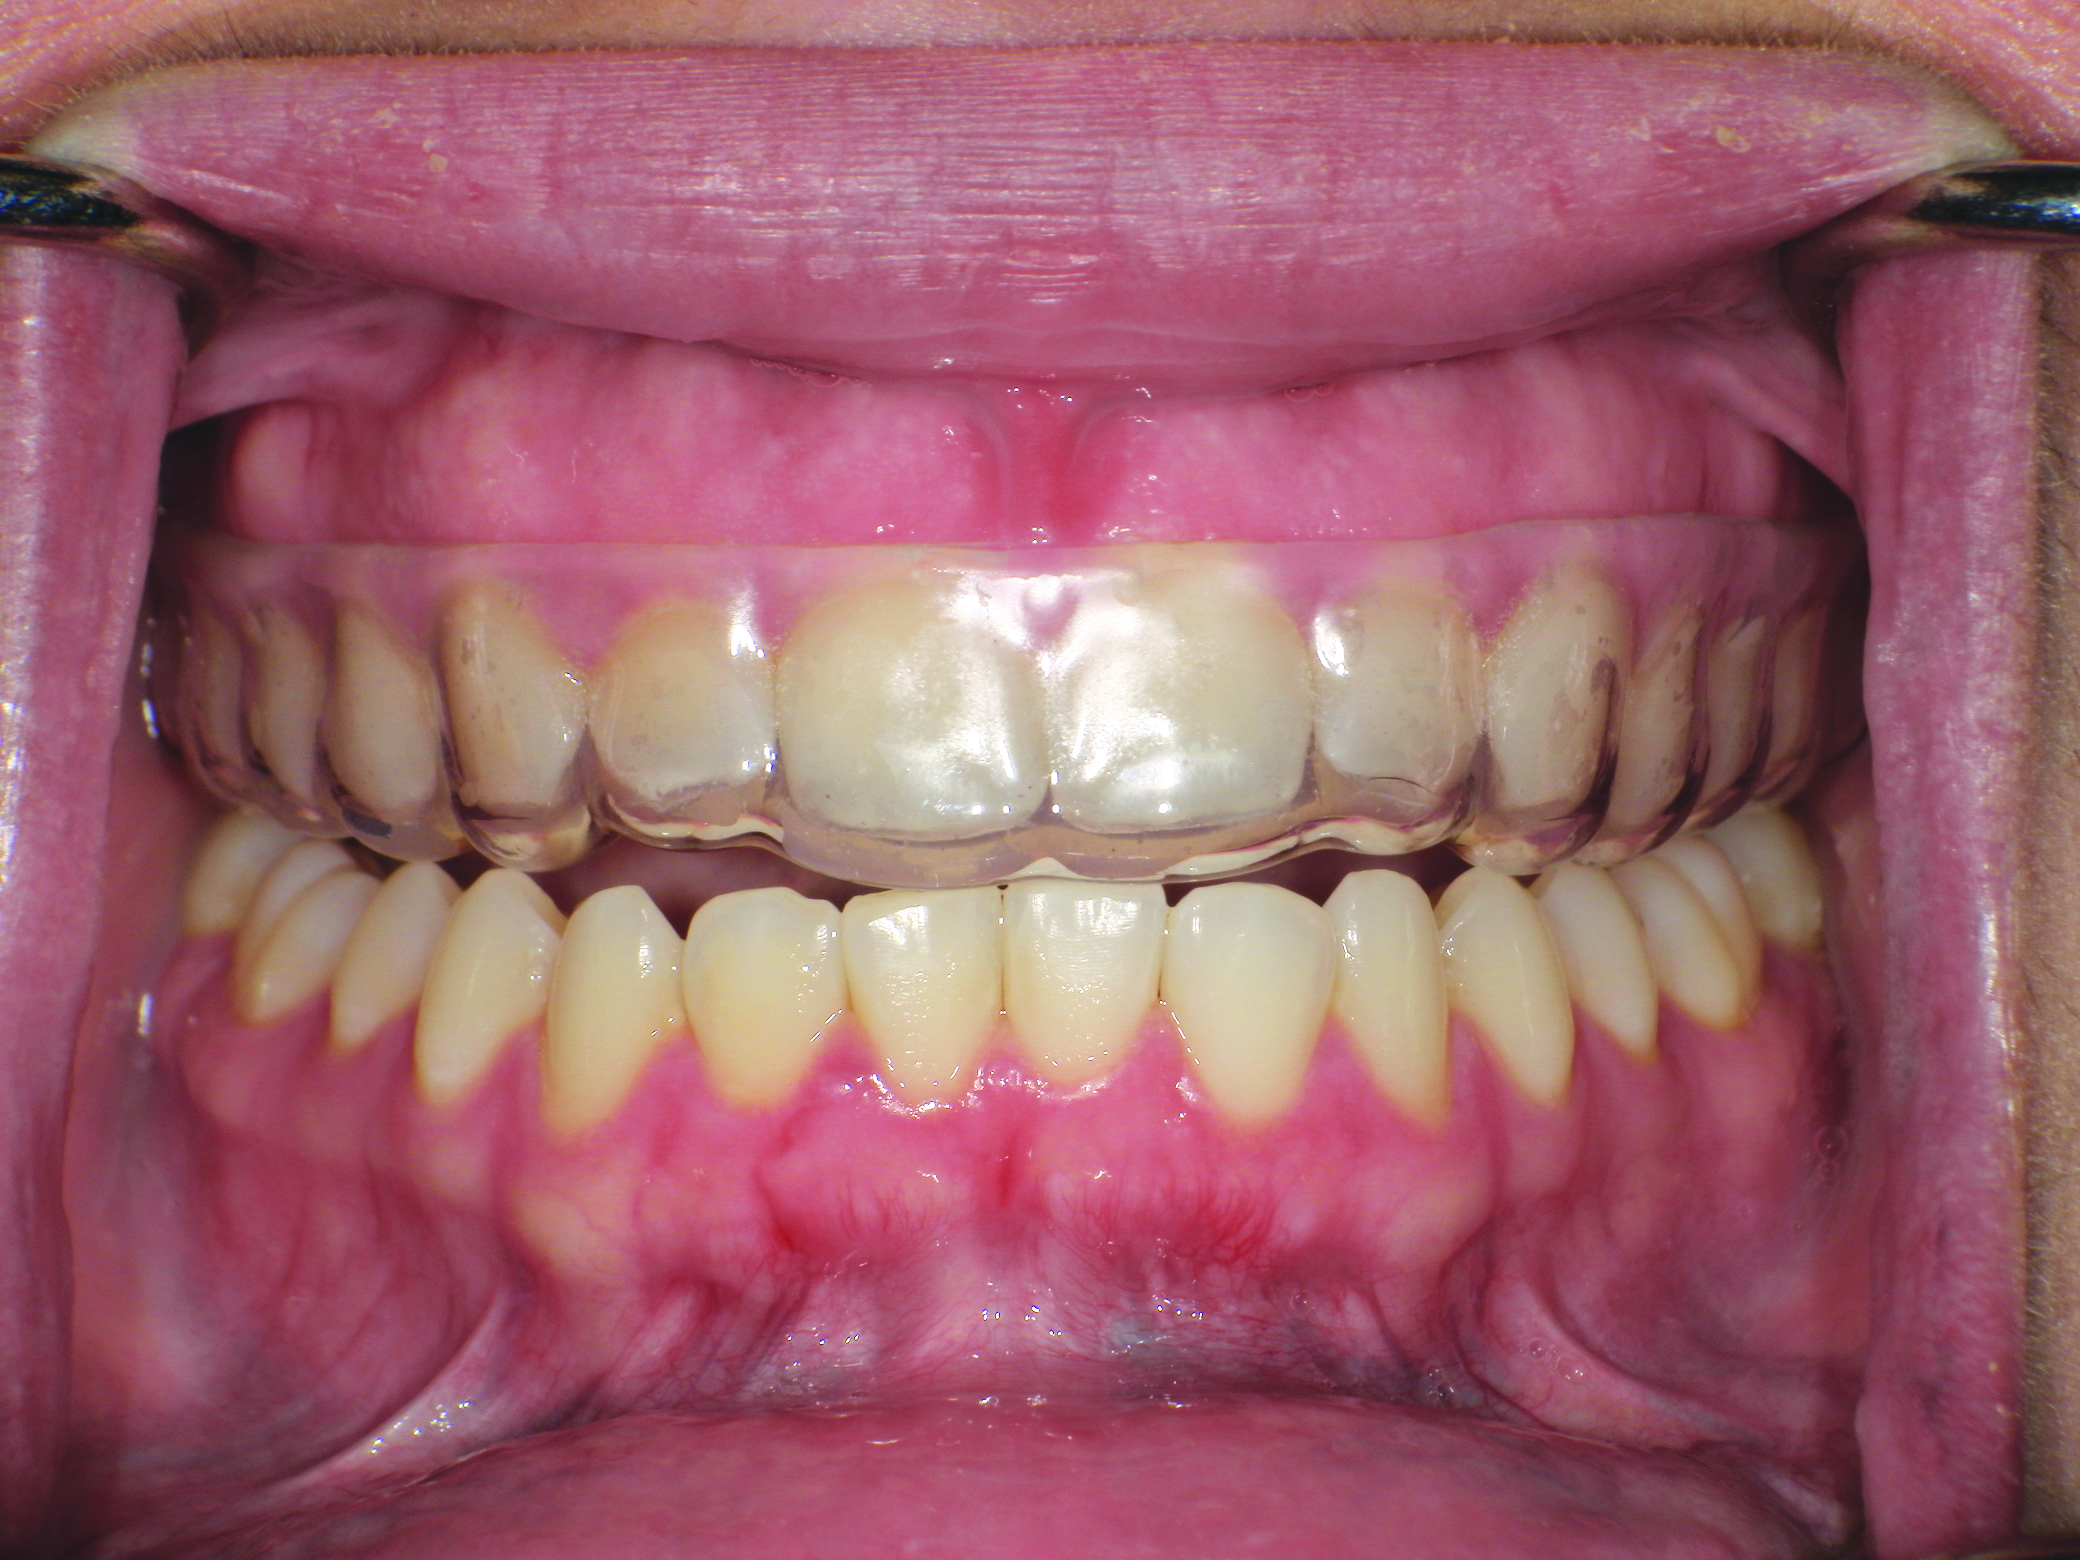

(8.) Retracted intraoral view and occlusal extraoral view, respectively, of the completed, dual-layer, custom-made sports mouth guard.

Figure 7

Figure 8

It should be noted that variation in the elastic modulus of the overlying laminate can significantly affect the device’s ability to prevent hard- and soft-tissue damage. Control over the thickness of in-office fabricated sports mouth guards can be obtained using combinations of inner and outer laminated layers.1 The finished product should have bilateral interocclusal contacts (Figure 7), cover all labial and lingual maxillary tooth surfaces, and have an open palate (Figure 8).